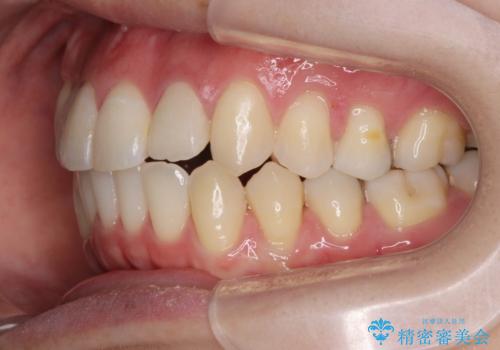

引っ込んだ前歯を並べたい マウスピースと部分ワイヤーのコンビネーション矯正

- 引っ込んで生えてしまっている前歯を並べたい、と矯正治療を希望され来院されました。

まずマウスピース矯正インビザラインシステムで、引っ込んだ歯が並ぶためのスペースを作ったのち、部分ワイヤー矯正を行い短期間での配列を計画します。

マウスピース・ワイヤーそれぞれの長所をうまく活かすことで治療期間の短縮が可能となります。

このように前歯の部分ワイヤーは引っ込んでしまった前歯や がたつきを素早く改善することができます。